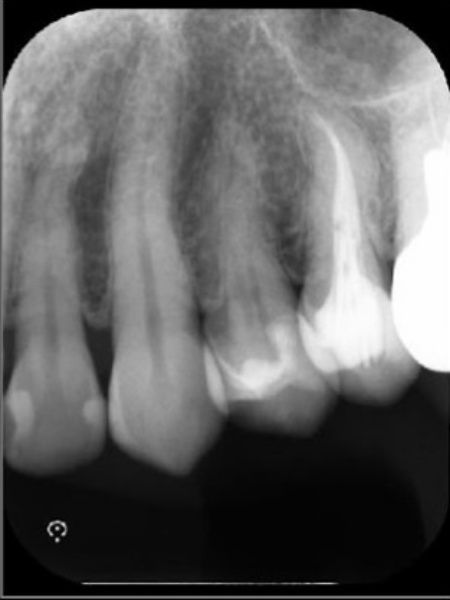

レントゲン検査を行って詳しく調べた結果、歯の根の先に歯の頭と同程度の大きさの根尖病巣(こんせんびょうそう)が確認できました。

根尖病巣とは歯の根の先にできる膿の袋のような病変です。

歯の内部の神経や血管が通る細い管に細菌感染が起こり、その影響が根の先に広がることで生じます。

治療終了から2年後のレントゲン画像です。根尖病巣が改善しています。